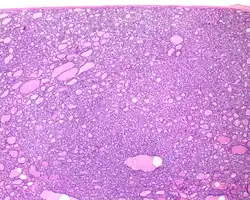

1) Encapsulated or partially encapsulated. The tumors are usually very well delimited or circumscribed, with the majority encapsulated, surrounded by a well formed fibrous connective tissue capsule.

3) Predominantly follicular pattern of growth. Papillary structures should not be present. Further, solid, insular, or trabecular architecture must be <30% of the overall tumor for this category to still apply. Colloid (the material that thyroid follicular cells create) is easily identified throughout.